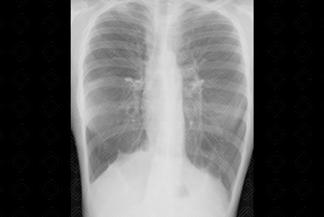

Texto alternativo para a imagem Figuras 1 e 2. Créditos: Dra. Elazir Mota - Rio de Janeiro/RJ

Descrição das figuras 1 e 2: Radiografia de tórax PA e perfil. Paciente do sexo feminino, 14 anos, com frequentes exacerbações da asma. Observa-se na radiografia alguns sinais de hiperinsuflação pulmonar, como coração em gota e aumento do espaço anteroposterior da caixa torácica, notadamente na região retroesternal (asterisco).

• Radiografia de tórax: O exame é normal na maioria dos casos. No entanto, nos casos mais graves e com exacerbações frequentes, pode-se observar: atelectasias, oligoemia periférica, espessamento de paredes brônquicas e sinais de hiperinsuflação pulmonar (como nas imagens acima);